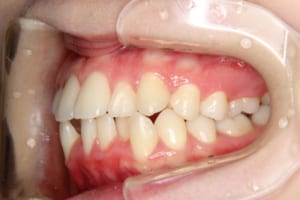

治療後

主訴 下の歯の凸凹

上の前歯が出ているのが気になる

治療期間 4年6か月

抜歯および非抜歯 上顎:右側中切歯、右側側切歯、左側第一小臼歯

下顎:両側第一小臼歯